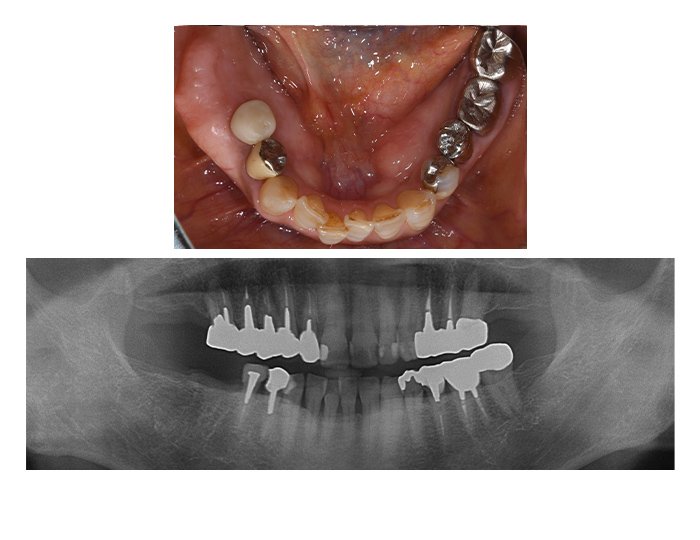

症例03 奥歯のインプラント3本(女性、期間9カ月)

BEFORE(術前)

AFTER(術後)